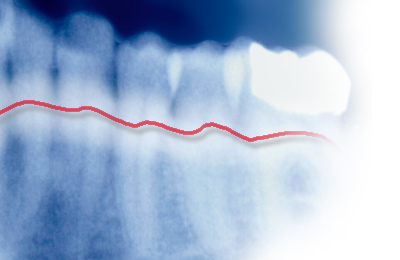

Zunächst erfolgt eine ausführliche Untersuchung zur Befundaufnahme Anamnese, bei der neben den akuten Symptomen auch (Vor-)Erkrankungen (z. B. Diabetes, Bluthochdruck), Medikamenteneinnahme und Gewohnheiten abgefragt werden. Wir erheben klinische und röntgenologische Befunde und messen die Taschentiefen.